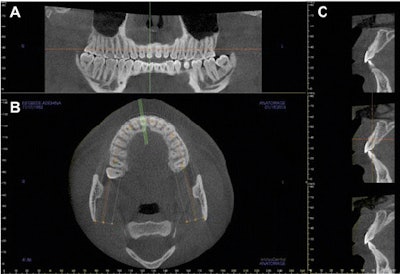

Researchers used a Kodak 9500 CBCT unit (Carestream Health), and scans were acquired at 90 kV, 10 mA, 16 sec, and a 0.2-mm3 voxel size. The CBCT images were reconstructed with Invivo 5.1 software (Anatomage) at 1-mm thickness. All included CBCT scans covered both maxillary and mandibular arches with a field-of-view (FOV) of 150 x 90 mm2.

The CBCT scans were checked and reorientated to ensure the occlusal plane was positioned parallel to the floor. Researchers took cross-sectional views perpendicular to the alveolar ridge in the middle of the maxillary right central incisor, lateral incisor, and canine regions. All the measurements were taken by one examiner.

The mean alveolar heights for the maxillary right central incisor, lateral incisor, and canine were 18.83 ± 3.23 mm, 19.07 ± 2.53 mm, and 18.91 ± 2.81 mm, respectively. Widths for incisors and canines are shown in the table below.